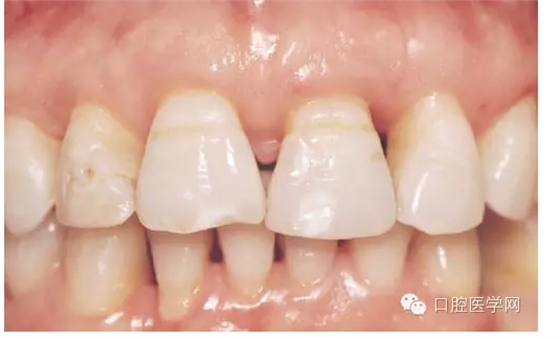

這里先發(fā)一張照片,是一個(gè)需要解決黑三角的病例。照片是在一國外文獻(xiàn)上截的(我很少看國內(nèi)的文獻(xiàn))。從照片上看,患者前牙去區(qū)基本都有黑三角的問題。那么是為什么會(huì)出現(xiàn)黑三角?